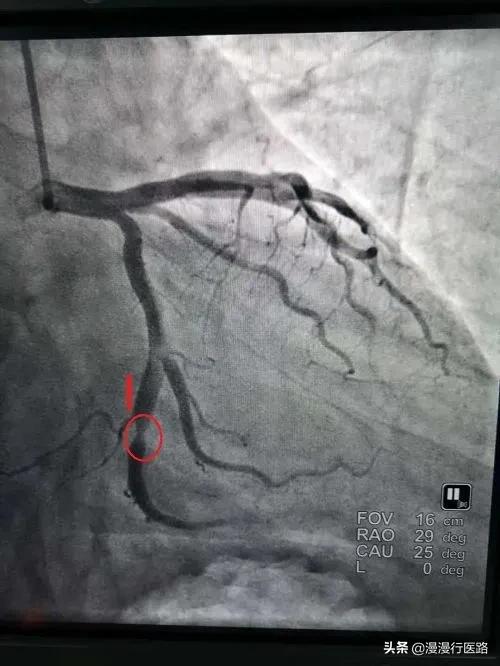

- Il existe trois artères coronaires principales dans le cœur, qui sont divisées en branche descendante antérieure, artère coronaire droite et branche circonflexe. Si un stent est placé dans l'un de ces vaisseaux en raison d'une sténose sévère, mais qu'il subsiste une sténose dans d'autres parties du corps, il se peut que le patient ne soit toujours pas apte à effectuer un travail physique.

J'ai alors fait procéder aux examens nécessaires et l'imagerie a montré que la sténose de l'artère coronaire gauche atteignait 85 %, ce qui nécessitait la pose d'un stent.

J'ai expliqué à M. Zhang : "M. Zhang, le degré de sténose de votre artère coronaire gauche a atteint 85%, et la dernière comparaison est manifestement sérieuse, pour répondre aux critères de mise en place de stents, vous devez l'envisager".